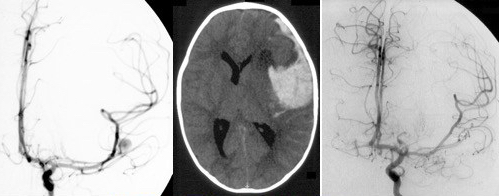

Il s’agit de lésions très rares. du fait de sa rareté, l’anévrisme rompu n’est souvent diagnostiqué qu’au moment du resaignement. Comme chez l’adulte, le traitement repose sur la chirurgie ou l’embolisation, les indications devant être discutées de façon pluridisciplinaire.

il repose sur la microchirurgie ou l’embolisation. Les avantages respectifs de l’un ou l’autre traitement sont à discuter au cas par cas. ces 2 traitements nécessitent des équipes entraînées pour la prise en charge des ces patients souvent en bas âge.